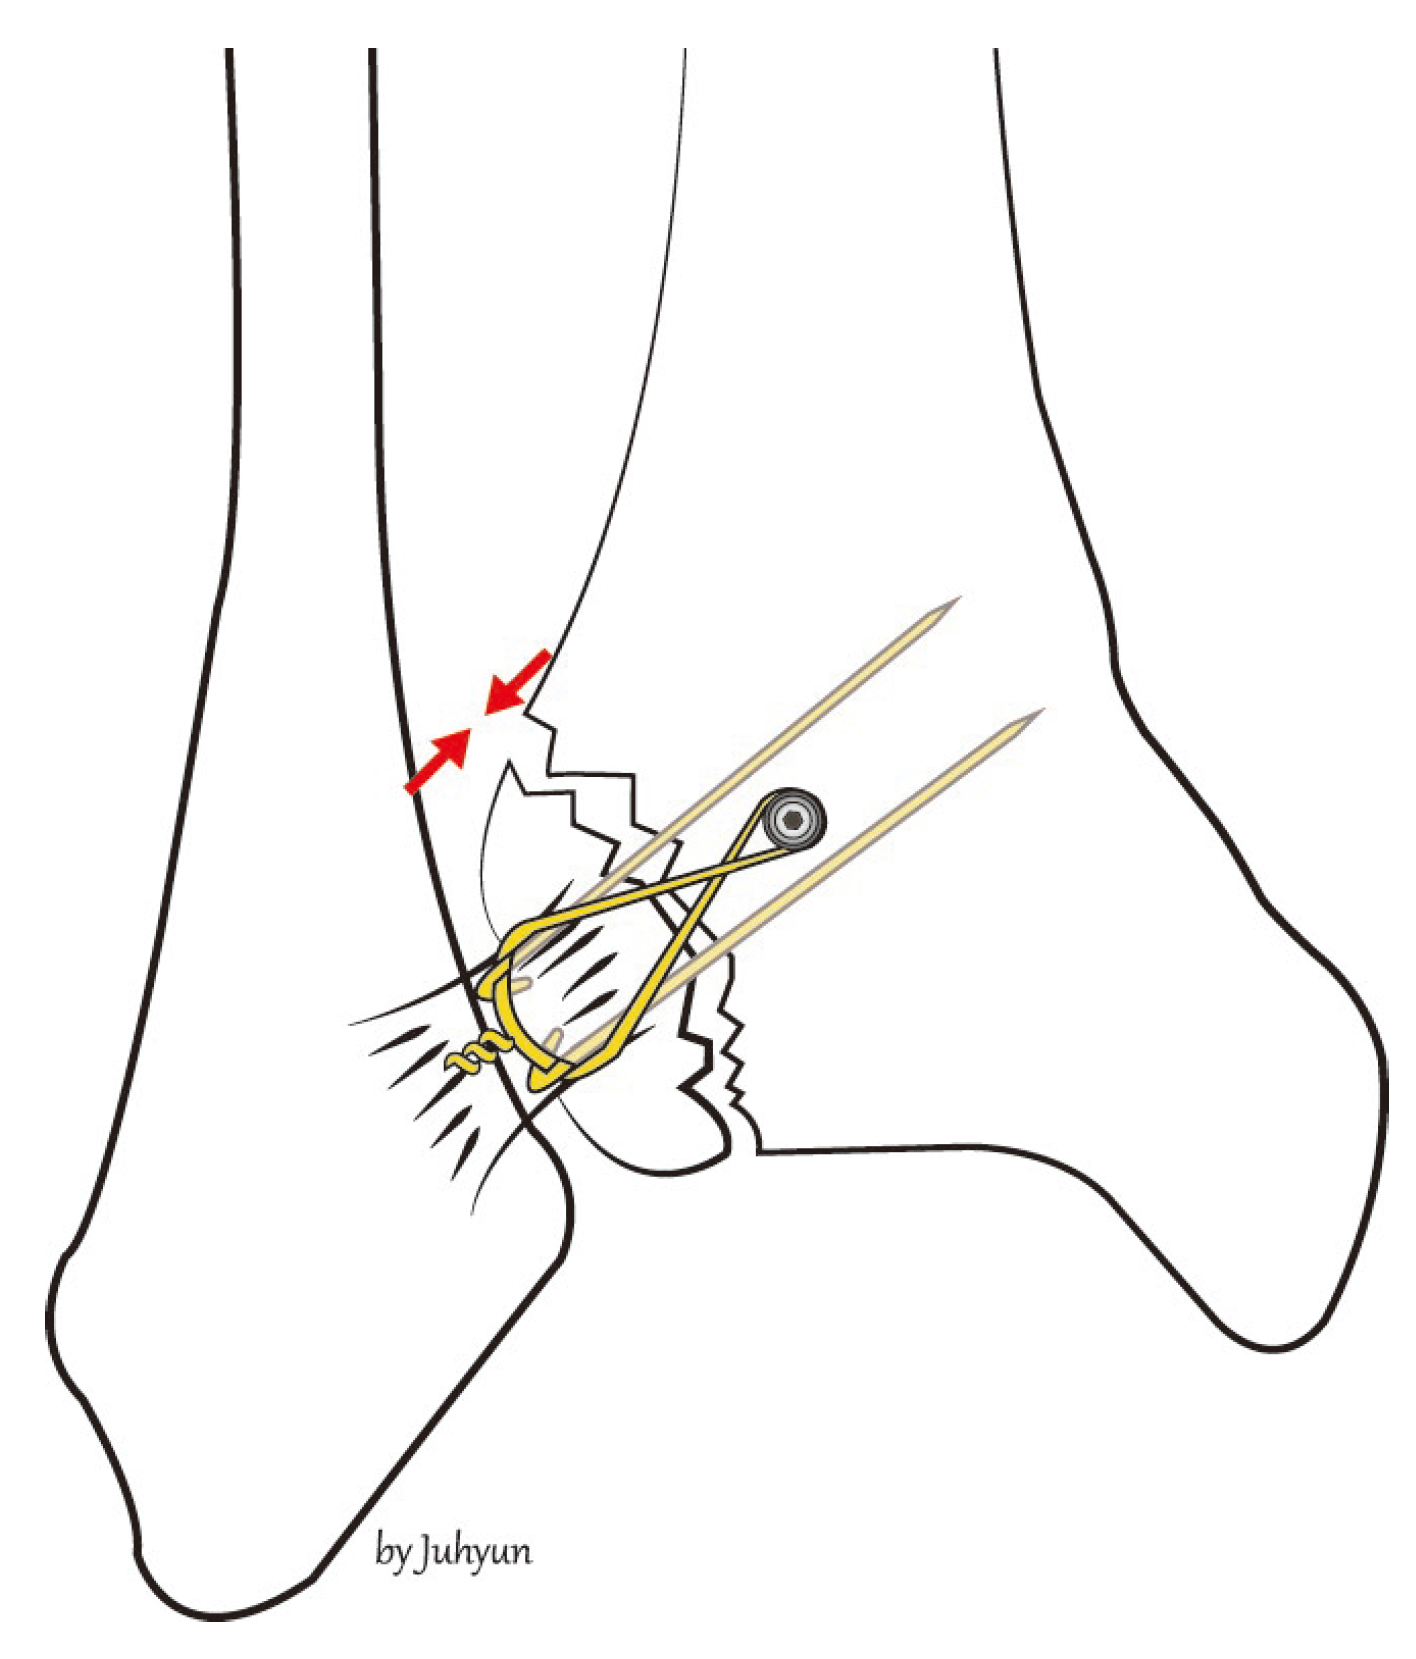

2. Surgical Technique